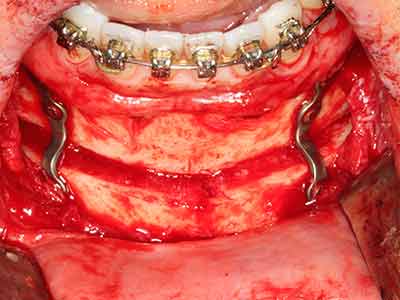

Piezosurgery has additional advantages when harvesting bone blocks. In addition to the high precision with osteotomy described above, the use of the thin saw tips specifically minimizes loss of material. Greater loss of material during harvesting can be expected with the thicker instrument tips, particularly when using Lindemann drills (Lakshmiganthan, Gokulanathan et al. 2012). The basal separation, which is necessary particularly for retromolar block transplants, is simplified by specially designed rectangular saws, with the result that piezosurgery is viewed as a precise, simple and safe procedure for harvesting retromolar bone blocks (Happe 2007) (Fig. 1-12).

Indication: Bone splitting

Bone tissue is not simply a mineral structure but also contains a substantial proportion of collagen fibres. This means it not only has good compressive strength but also a degree of flexibility, which can be taken advantage of when performing bone augmentations. In the classical expansion procedure using bone splitting, the atrophied alveolar ridge is split longitudinally and carefully expanded after reaching an adequate osteotomy depth (Fig. 13-16), ideally without substantial removal of the periosteum (Brugnami, Caiazzo et al. 2014, Stricker, Fleiner et al. 2014). Screw and plate systems with increasing expansion distance have proven effective in separating the two bone lamellae while remaining below the fracture threshold. In general, residual bone widths of at least 3–4 mm are required (Chiapasco, Zaniboni et al. 2006) to guarantee adequate flexibility and sufficient bone coverage of the future implants. If necessary, a vertical relief osteotomy on one or both sides can improve flexibility. A combination with additional augmentation techniques, particularly on the buccal side, has been described as an alternative to the classical technique.

The splitting procedure is particularly atraumatic and there is no significant loss of dimension when using piezosaws, and there are no significant differences between implants in split jaws and implants in an alveolar ridge without a bone deficit (Chiapasco, Zaniboni et al. 2006, Danza, Guidi et al. 2009). However, sufficient continuous irrigation is essential, particularly with locally restricted and deep splitting to prevent thermal stress in the apical osteotomy regions.